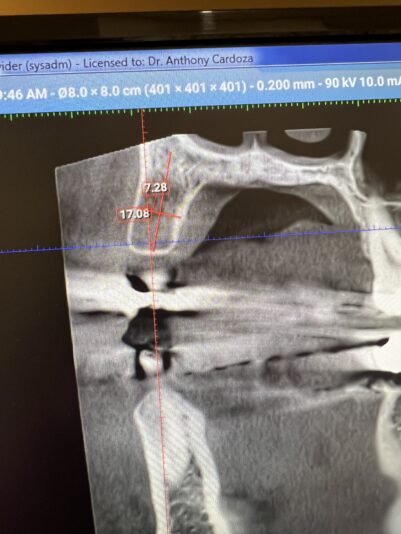

Dustin replied to the discussion Single implant tx planning in the forum Implant Tx Planning 2 years ago

Appreciate the reply and information! Looking at the mental it doesn’t seem like it issue but when you see exit on the buccal side it looked like the 10.5mm got a little close. But that’s all great info. Thank you